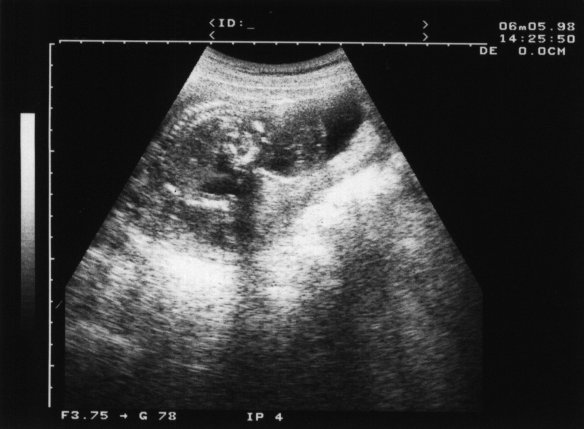

98年6月5日(妊娠15週4日)

おぉ! 背骨が写ってる!! なんか魚の骨みたい.^o^

背骨の左下が頭だそうな. 言われて見ればそんな気もしないではないが...